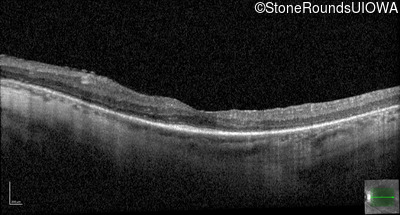

Optical Coherence Tomography - Right - 20/50 -2

Exemplar / OCT Stack